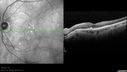

80-year-old woman noticed decreasing vision for sometime between the last six to twelve months. She is a voracious reader. She finds she is having difficulty reading and seeing well. You saw a problem with the retina and suggest she come here for an evaluation. She also was told that you were considering laser for posterior capsular opacities. VISUAL ACUITY: OD 20/40, OS 20/63. IOP: OD 12, OS 13. SLIT EXAMINATION: The posterior chamber intraocular lens is in good position in both eyes. EXTENDED OPHTHALMOSCOPY: OD: Vertical C/D ratio is 0.3. There is posterior vitreous separation. There is hemorrhage inferotemporal to the fovea with subretinal fluid. OS: Vertical C/D ratio is 0.3. There is posterior vitreous separation and 2+ macular drusen. SPECTRALIS-SD-OCT SCAN: The OCT scan of the right eye shows intraretinal and subretinal fluid as well as pigment epithelium thickening inferotemporal to the fovea. The OCT scan of the left eye does show patchy drusen, but there is no intraretinal or subretinal fluid. Photos confirm clinical findings. FUNDUS AUTO FLUORESCENCE: The infra red and auto fluorescence images show reticular macular disease. FLUORESCEIN ANGIOGRAPHY: Fluorescein angiography of the right eye shows an occult subfoveal choroidal neovascular membrane a disc area in size centered inferotemporal to the fovea, which leaks in the late frames. The angiogram of the left eye shows a few hyperfluorescence spots around the macula, which stain, but don’t leak. INDOCYANINE GREEN ANGIOGRAPHY: The indocyanine green angiogram shows a disc area of neovascular membrane inferotemporal to the fovea. There is no evidence of any polypoidal choroidal vasculopathy. In the left eye the indocyanine green angiogram shows no leakage and all the testing does show significant reticular pseudo drusen. IMPRESSION: 1. WET AGE-RELATED MACULAR DEGENERATION – RIGHT EYE 2. OCCULT SUBFOVEAL CHOROIDAL NEOVASCULAR MEMBRANE - RIGHT EYE 3. MACULAR HEMORRHAGE – RIGHT EYE 4. PIGMENT EPITHELIAL DETACHMENT – RIGHT EYE 5. RETICULAR MACULAR DISEASE – BOTH EYES DISCUSSION: I explained to the patient the right eye does have wet age-related macular degeneration. With Avastin there is a 90 percent chance of improving the vision some and a 50 percent chance of improving the vision a lot. I explained to her that all the treatments are safe and effective. It does often require ongoing therapy at least for a while.

Reticular Macular Disease (Pseudo-drusen) Both Eyes - Occult CNVM and Macular Edema Right Eye 543 viewsSpectral Domain Optical Coherence Tomography00000

Reticular Macular Disease (Pseudo-drusen) Both Eyes - Occult CNVM and Macular Edema Right Eye 546 viewsSpectral Domain Optical Coherence Tomography00000

Reticular Macular Disease (Pseudo-drusen) Both Eyes - Occult CNVM and Macular Edema Right Eye 612 viewsSpectral Domain Optical Coherence Tomography00000

Reticular Macular Disease (Pseudo-drusen) Both Eyes - Occult CNVM and Macular Edema Right Eye 606 viewsSpectral Domain Optical Coherence Tomography00000

Reticular Macular Disease (Pseudo-drusen) Both Eyes - Occult CNVM and Macular Edema Right Eye 603 viewsSpectral Domain Optical Coherence Tomography00000

Reticular Macular Disease (Pseudo-drusen) Both Eyes - Occult CNVM and Macular Edema Right Eye 562 viewsSpectral Domain Optical Coherence Tomography00000

Reticular Macular Disease (Pseudo-drusen) Both Eyes - Occult CNVM and Macular Edema Right Eye 1277 viewsSpectral Domain Optical Coherence Tomography00000

Reticular Macular Disease (Pseudo-drusen) Both Eyes - Occult CNVM and Macular Edema Right Eye 778 viewsSpectral Domain Optical Coherence Tomography00000